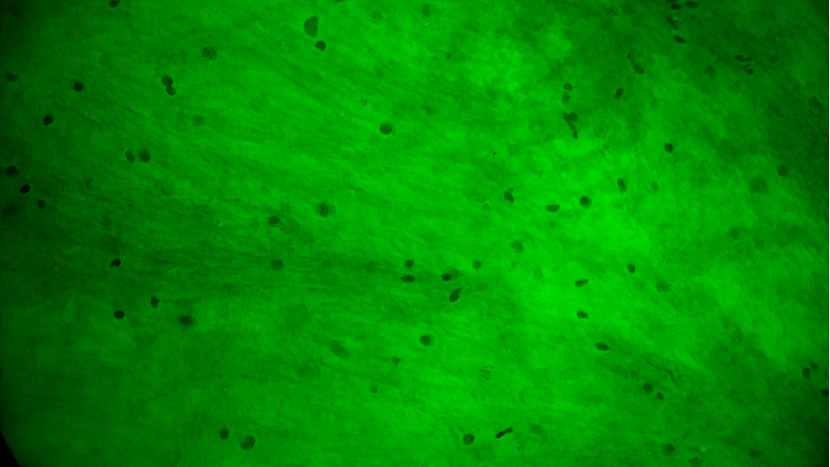

術(shù)中EndoSCell?細胞圖像如下:

可疑組織的腫瘤細胞殘留:細胞核異型性顯著,分布密集且不規(guī)則